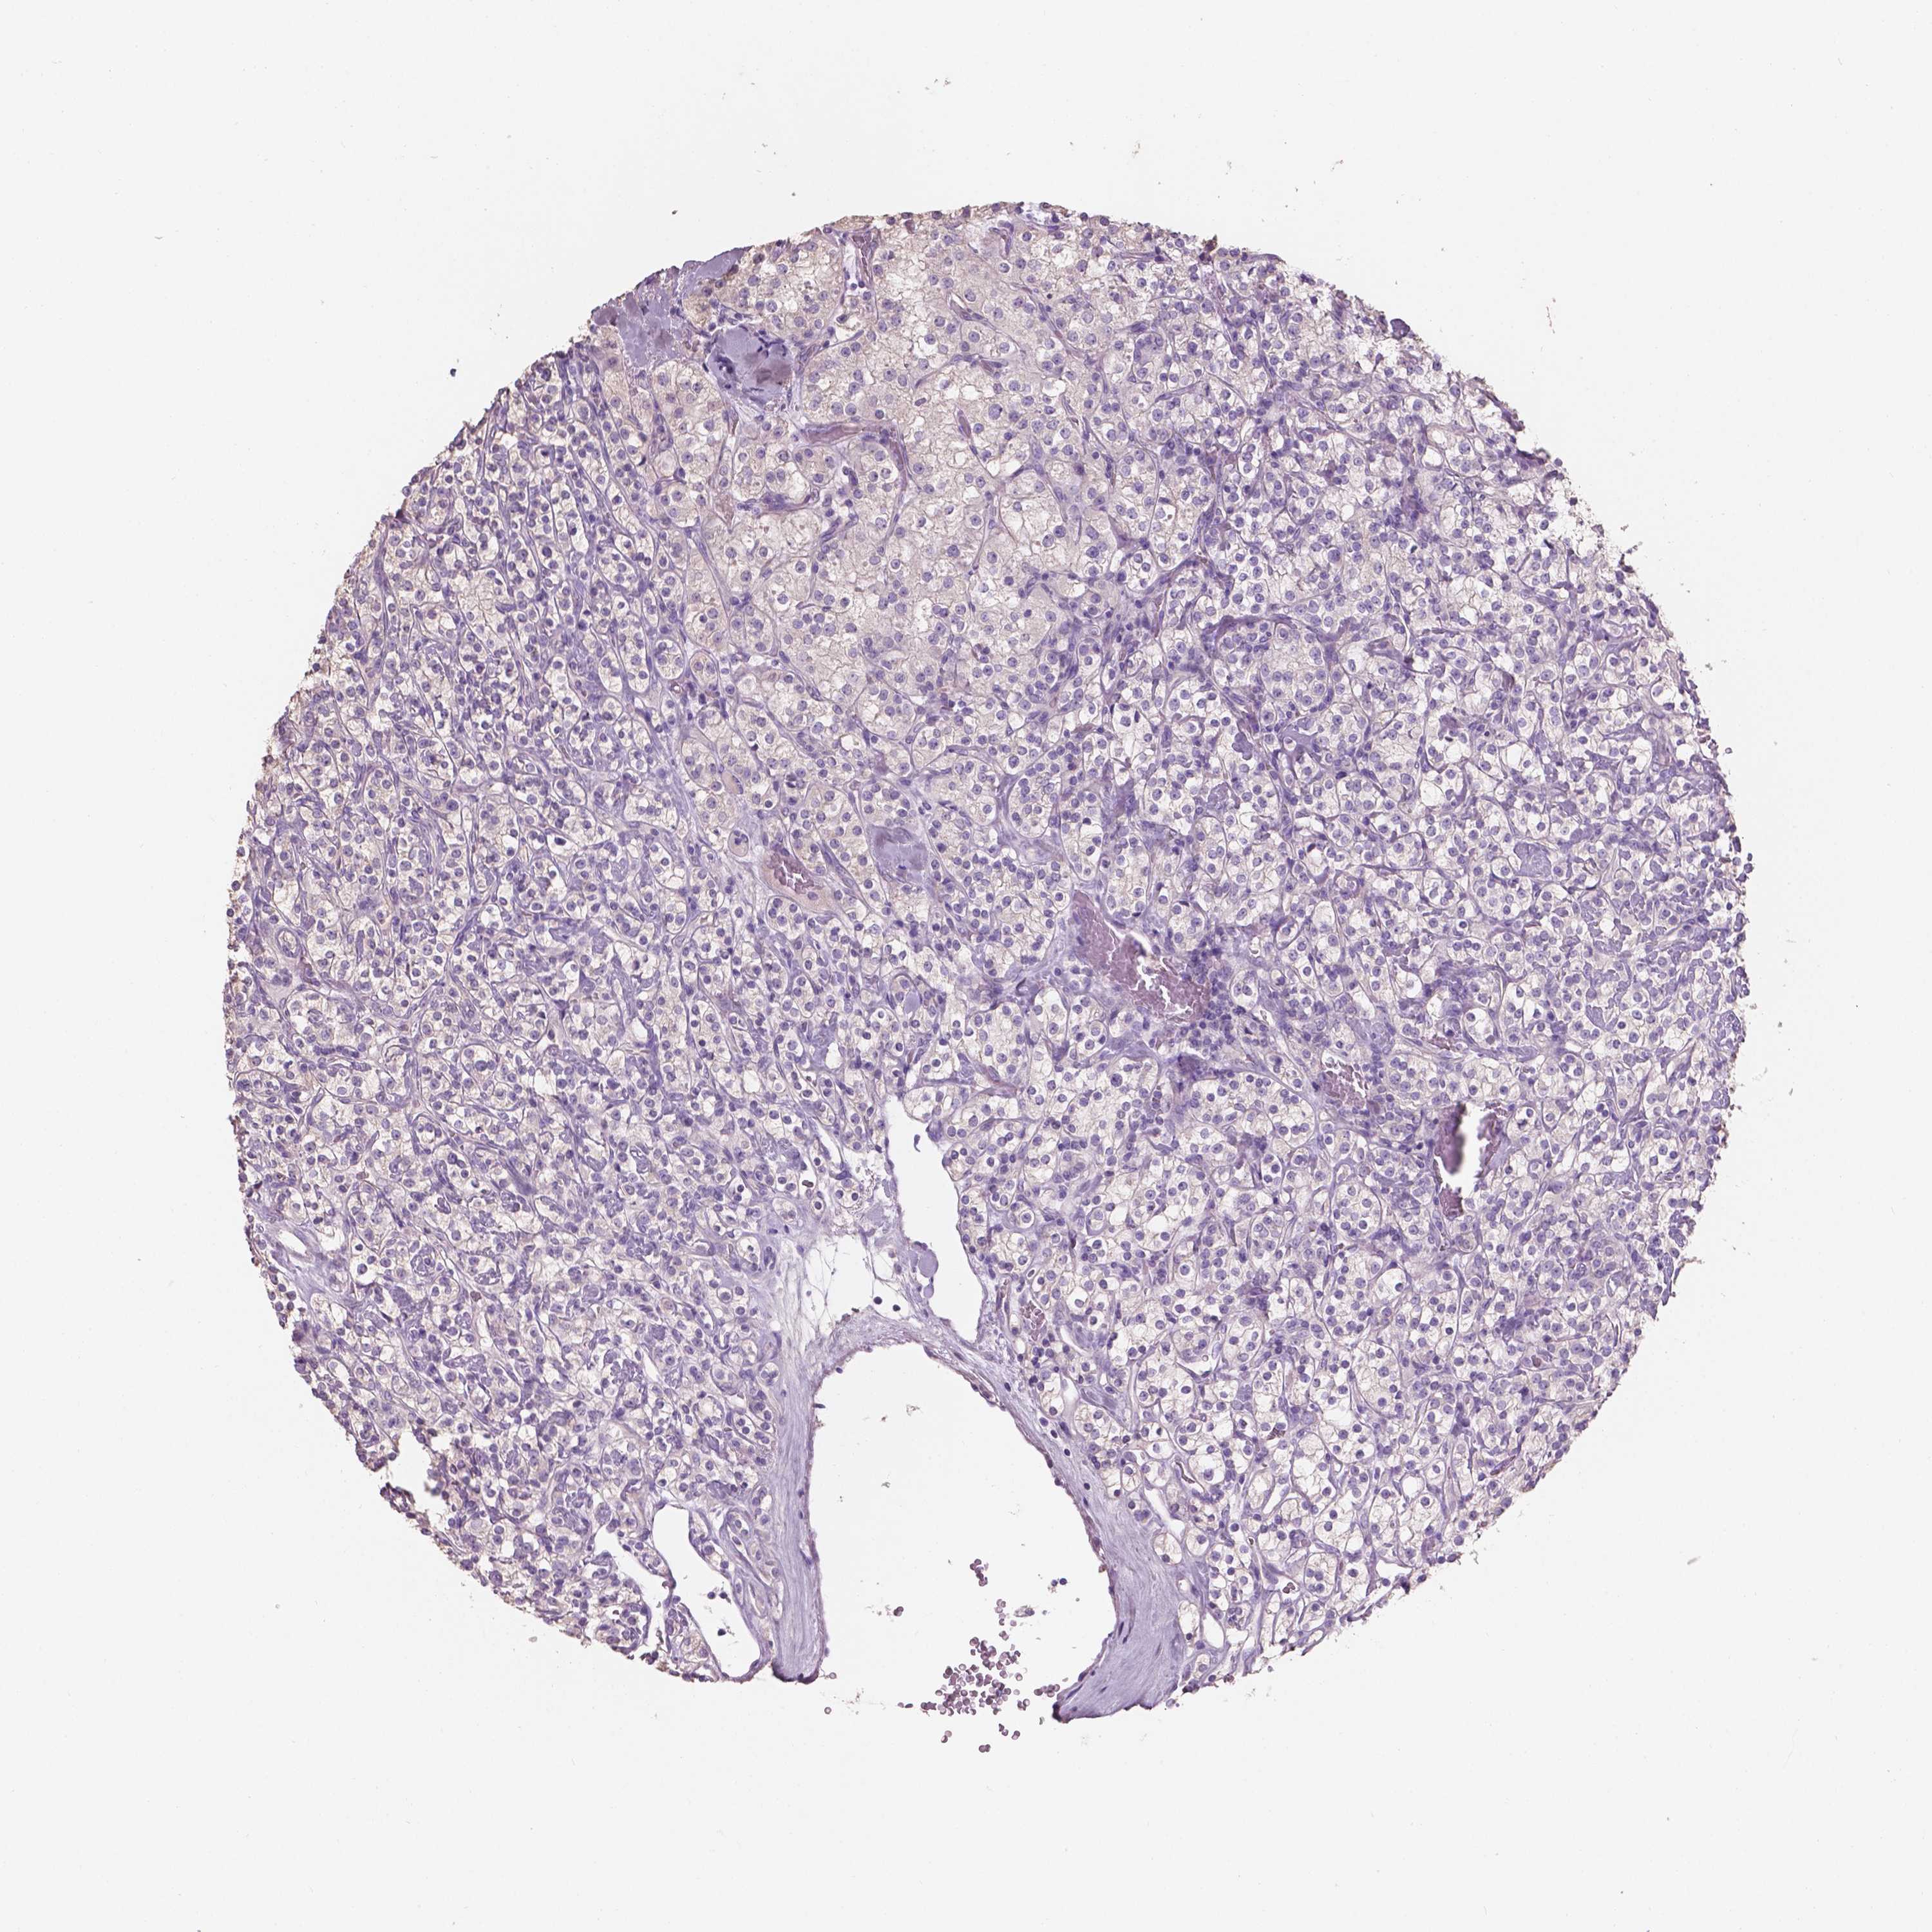

CANCER RENAL CANCER Show tissue menu

KICH TCGA KIRC TCGA KIRC VALIDATION KIRP TCGA PROTEIN RCC CPTAC PROTEIN EXPRESSION